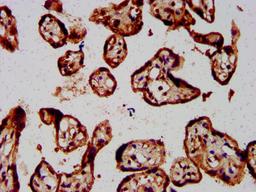

IHC image of CSB-PA008784LA01HU diluted at 1:800 and staining in paraffin-embedded human placenta tissue performed on a Leica BondTM system. After dewaxing and hydration, antigen retrieval was mediated by high pressure in a citrate buffer (pH 6.0). Section was blocked with 10% normal goat serum 30min at RT. Then primary antibody (1% BSA) was incubated at 4°C overnight. The primary is detected by a biotinylated secondary antibody and visualized using an HRP conjugated SP system.